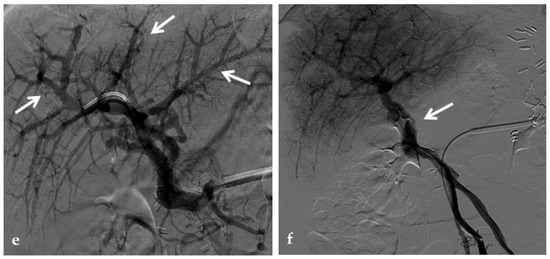

Figure 11.

Anteroposterior view of a percutaneous transmesenteric portography imaging series of an acute complete portal vein thrombosis occurred early after pediatric split-liver transplantation in a 1-year-old female with biliary atresia. (a) Superior mesenteric portography performed through a surgically-placed transmesenteric sheath (white arrow) shows total occlusion of the main portal vein and its intrahepatic branches, with opacification of several portosystemic varices (black arrows). (b) Superior mesenteric portography shows effective embolization of the portosystemic shunts to reduce the flow-steal phenomenon. A mixture of N-butyl cyanoacrylate and iodized oil and metallic microcoils (arrows) were used. (c) Portography image shows angioplasty with a 5-mm non-compliant balloon catheter performed on a stiff guidewire advanced through the common portal vein (white arrow). Note the spontaneous remaining opacification caused by the mixture of N-butyl cyanoacrylate and iodized oil (black arrows). (d) Final superior mesenteric portography shows restored opacification of the portal vein anastomosis, the umbilical recess of the portal vein (black arrow) and the intrahepatic segment 2 and segment 3 branches (white arrows), with no contrast filling of the portosystemic shunts.

Stenosis and thrombosis of the bypass graft typically occur weeks to years after surgery and may be clinically evident with recurrence of portal hypertension and impaired liver function tests. Thrombosis or high-grade stenosis represents the main cause of bypass graft occlusion. CT may show a low-density cord, representing the occluded bypass. CDUS can show the thrombus with a hypoechoic appearance associated with an absence of portal flow. In these situations, stenosis and thrombosis can be treated with transhepatic, transsplenic, or transmesenteric portography and angioplasty. Balloon dilation can be performed when the transtenotic pressure gradient is greater than 5 mmHg or when a stenosis is radiologically confirmed [66] (Figure 14).

Figure 14.

Anteroposterior view of a percutaneous transsplenic portography imaging series of an occluded Meso-Rex bypass in the same patient of Figure 8. (a) Percutaneous transsplenic portography shows extensive jejunal and gastric varices (arrows), with no opacification of the Meso-Rex bypass. (b) After superior mesenteric vein catheterization, portography shows the portal cavernoma (arrow) with no opacification of the native intrahepatic portal branches (whose patency was documented with retrograde portography in Figure 8). (c) Portography image shows successful recanalization of the mesenteric anastomosis of the Meso-Rex bypass (white arrow), with intrahepatic portal branches opacification (black arrows). (d) X-Ray image shows angioplasty of the bypass performed through a 9-mm non-compliant balloon catheter. During angioplasty, a focal notch (arrow) representing the mesenteric anastomotic stenosis is clearly visible. (e) Portography image acquired after bypass recanalization and angioplasty shows regular opacification of the intrahepatic portal system (arrows). (f) Portography image from the superior mesenteric vein shows a re-expanded Meso-Rex bypass with complete opacification in the mesenteric anastomotic tract (arrow). The intrahepatic portal system is regularly represented; the portal cavernoma and gastro-jejunal varices disappeared.